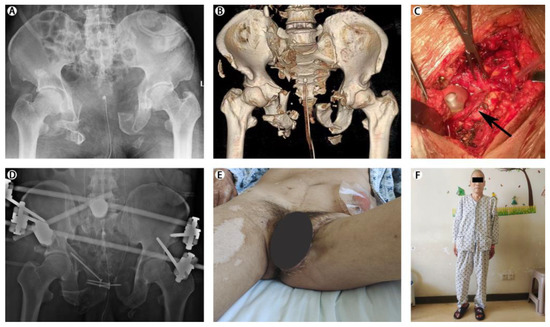

2. Materials and Methods

2.3. Management